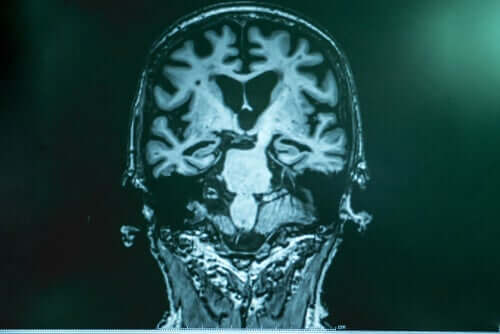

O Doutor Lopera explica que, no Alzheimer, há uma espécie de acúmulo de “resíduos” no cérebro. Os mesmos são compostos por uma proteína chamada amiloide. Os fragmentos desta proteína se unem e formam algo como uma “cola” que se adere aos neurônios e desencadeia uma cascata de falhas. A outra parte dos “resíduos” é o tau, que envolve o neurônio, o fecha e mata. O tau é mais nocivo.

Depois de conduzir estudos minuciosos em Boston, os especialistas comprovaram que o cérebro da paciente estava repleto de amiloide, inclusive mais do que em outros casos. No entanto, tinha muito pouco tau. As pesquisas permitiram comprovar que essa paciente tinha outra mutação que inibia a produção de tau e, com isso, atrasava o avanço da doença.